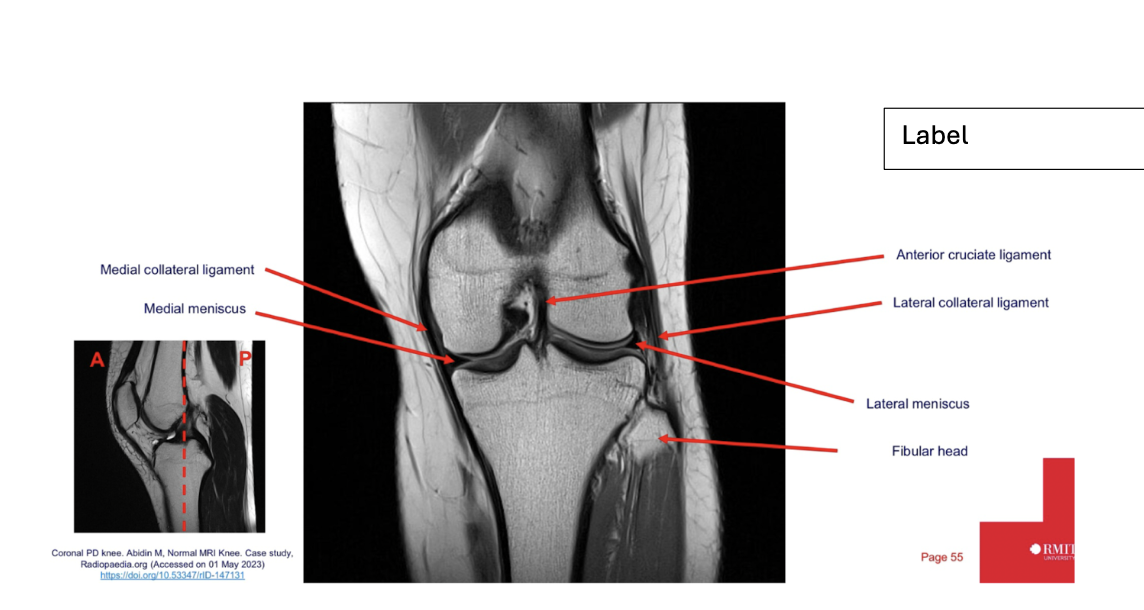

Sequence + pathology?

• 1st = PD: intermediate signal from muscle and fat is bright, image quality is much better

• 2nd = PD FS: fat has been supressed appearing much darker

• Path = complete ACL tear: in a normal knee you would see a black band which is the acl sitting

across the anterior aspect of the tibia and extending to the posterior aspect on the femur. This is not present at all hence, a tear.